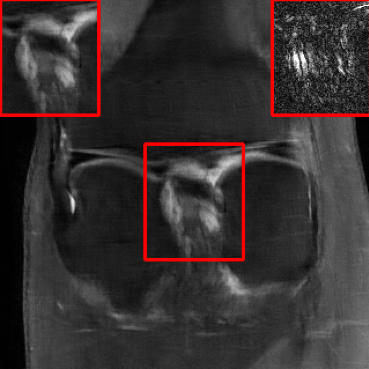

Results for the DIDN-based Reconstructor: To demonstrate adaptability to different network architectures, Table II compares reconstruction performance on the test set with the DIDN denoiser-based MoDL architecture. Average PSNR values with LONDN-MRI are compared to those with networks trained globally at different training set sizes. We ran only iteration of LONDN-MRI, where the reconstruction with a pre-trained (global) network was used to find neighbors. PSNR values for the oracle LONDN-MRI reconstructor are also shown. The overall performances with the DIDN-based architectures are better than with the UNet-based unrolled networks. The PSNRs for LONDN-MRI are consistently and similarly better than for the globally trained network across the different training set sizes considered, indicating potential for LONDN-MRI in improving state-of-the-art models. Fig. 6 visually compares reconstructions and reconstruction errors (in zoomed in region) for different methods. We can see that the LONDN reconstructors capture the original image features more sharply and accurately than the globally learned reconstruction.

| Ground Truth | Global | LONDN-MRI | Oracle |

| (1 iteration) | |||

![]() |

| PSNR = dB | PSNR = 34.15 dB | PSNR = 34.46 dB | PSNR = 34.54 dB |